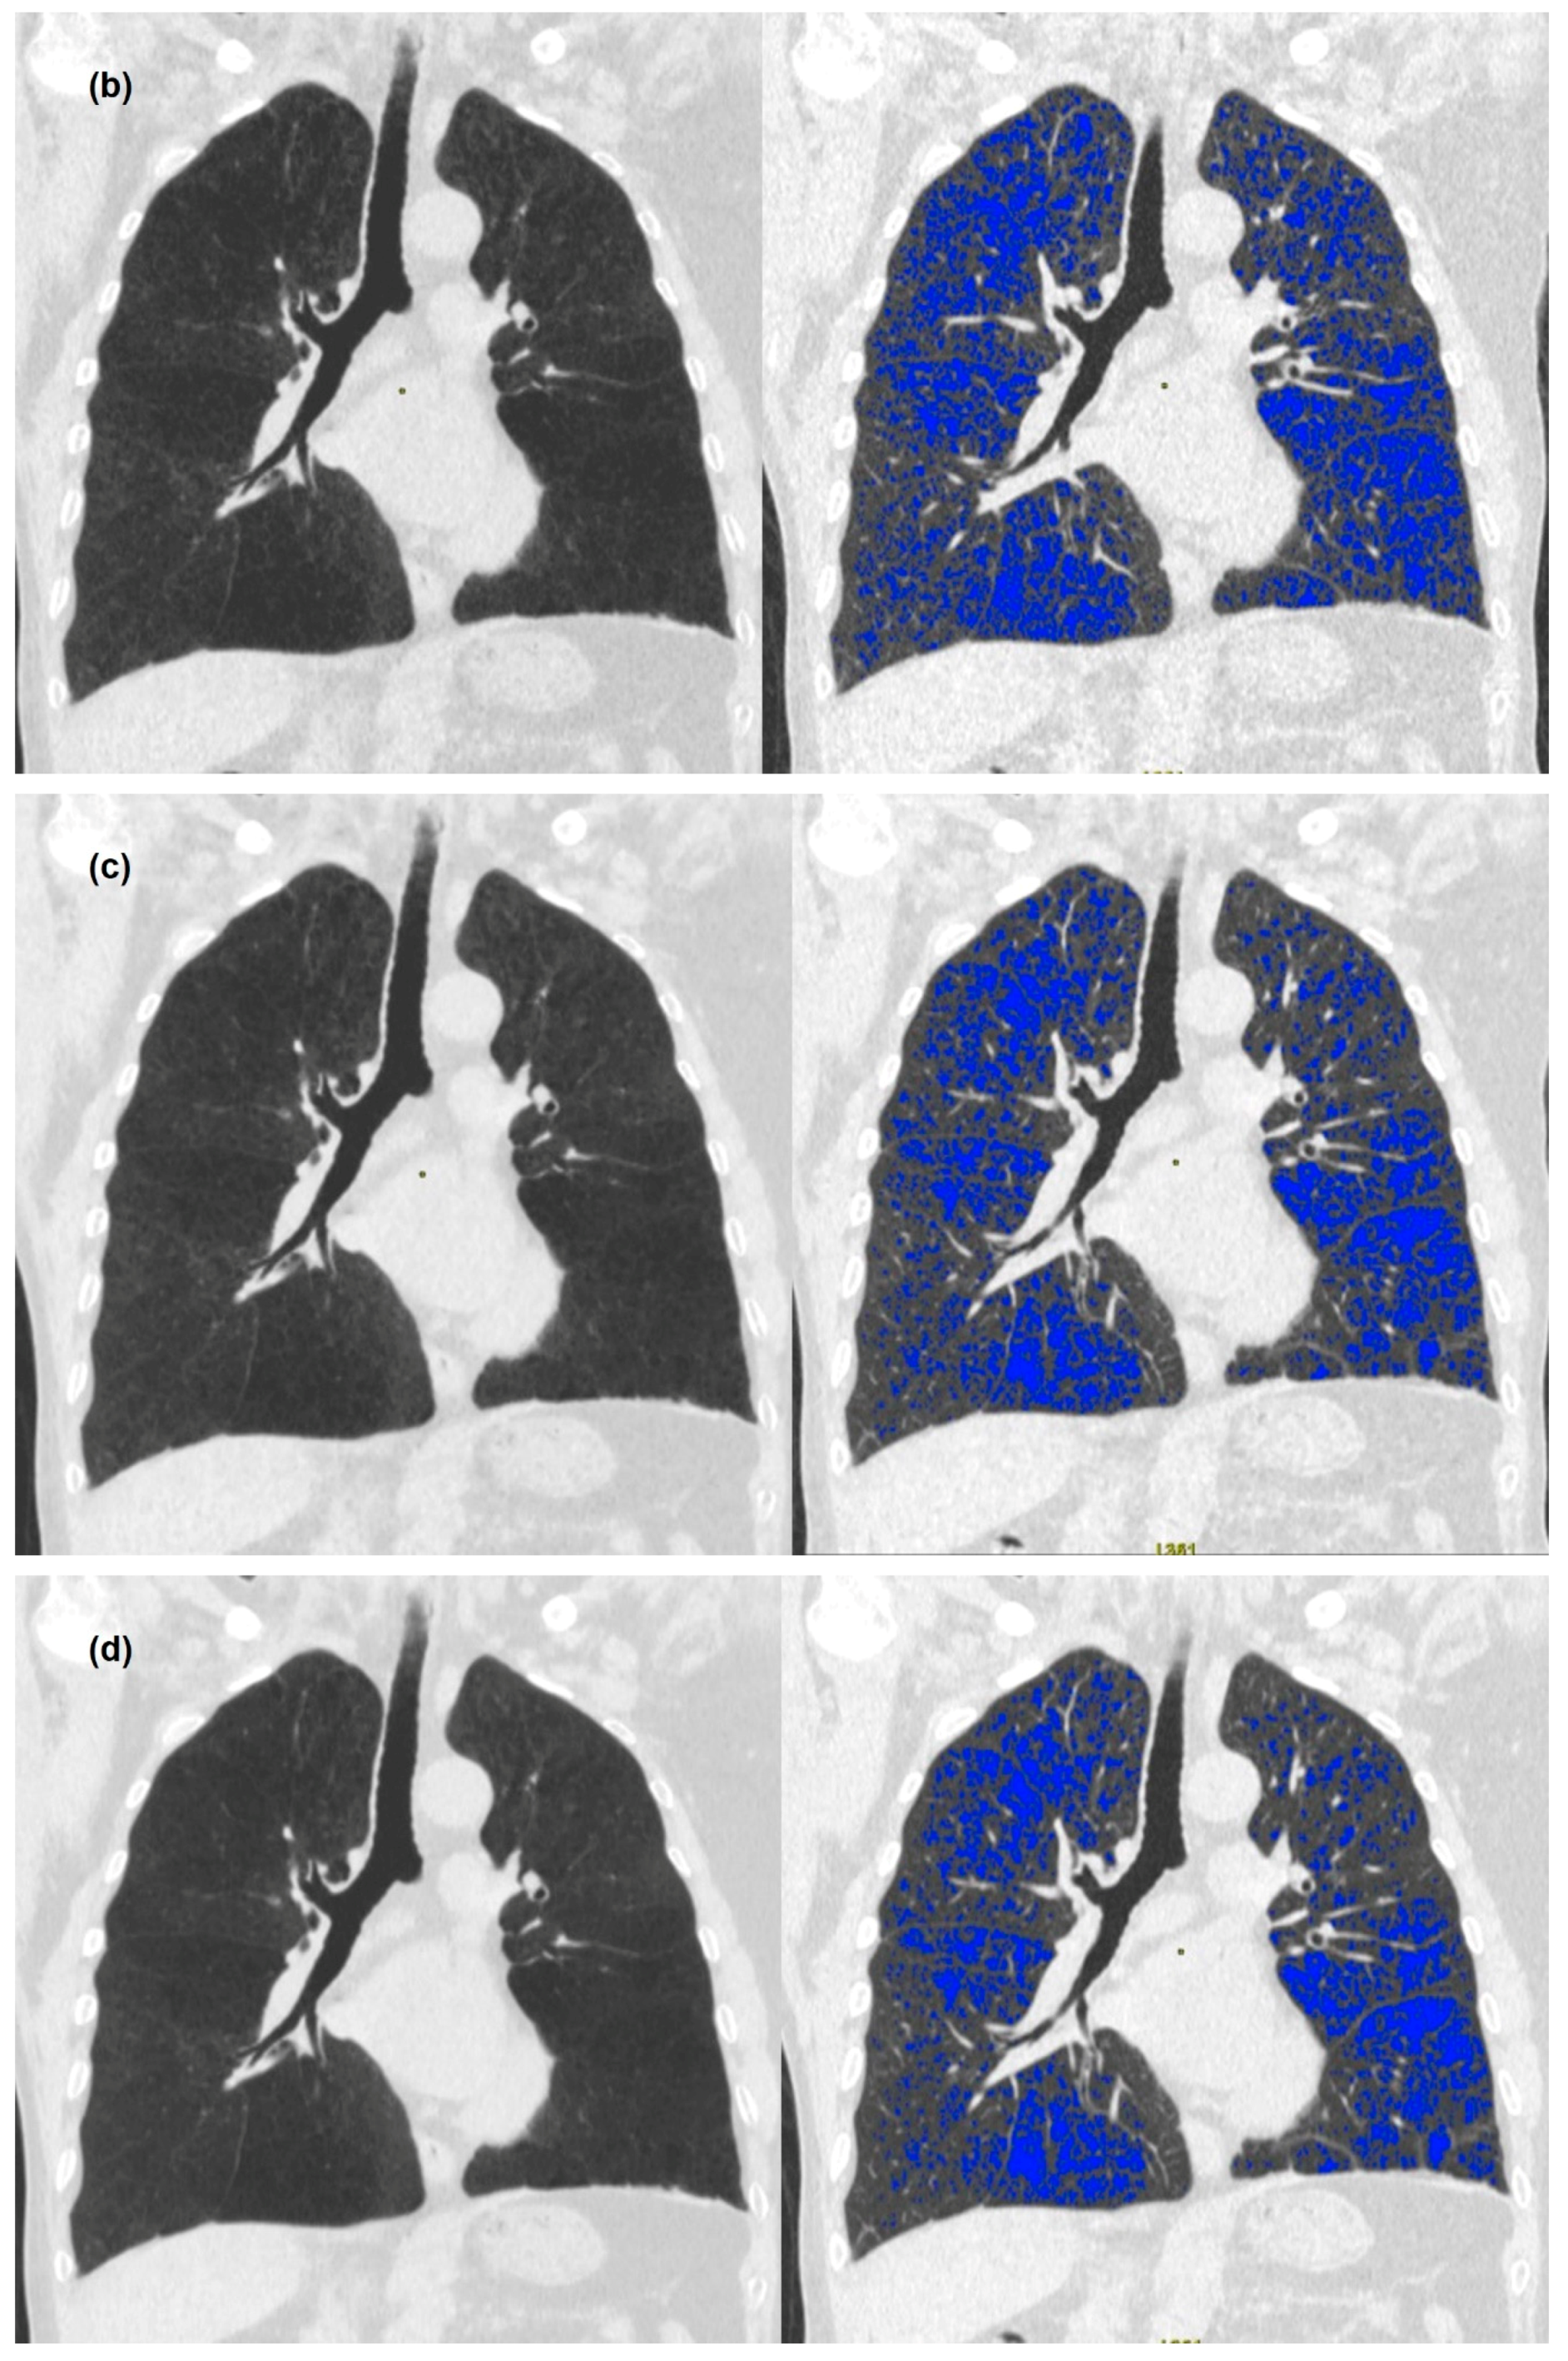

2.3. Image Analysis

3. Results

3.2. Quantitative Measurements of Standard-Dose and Ultra-Low-Dose CT